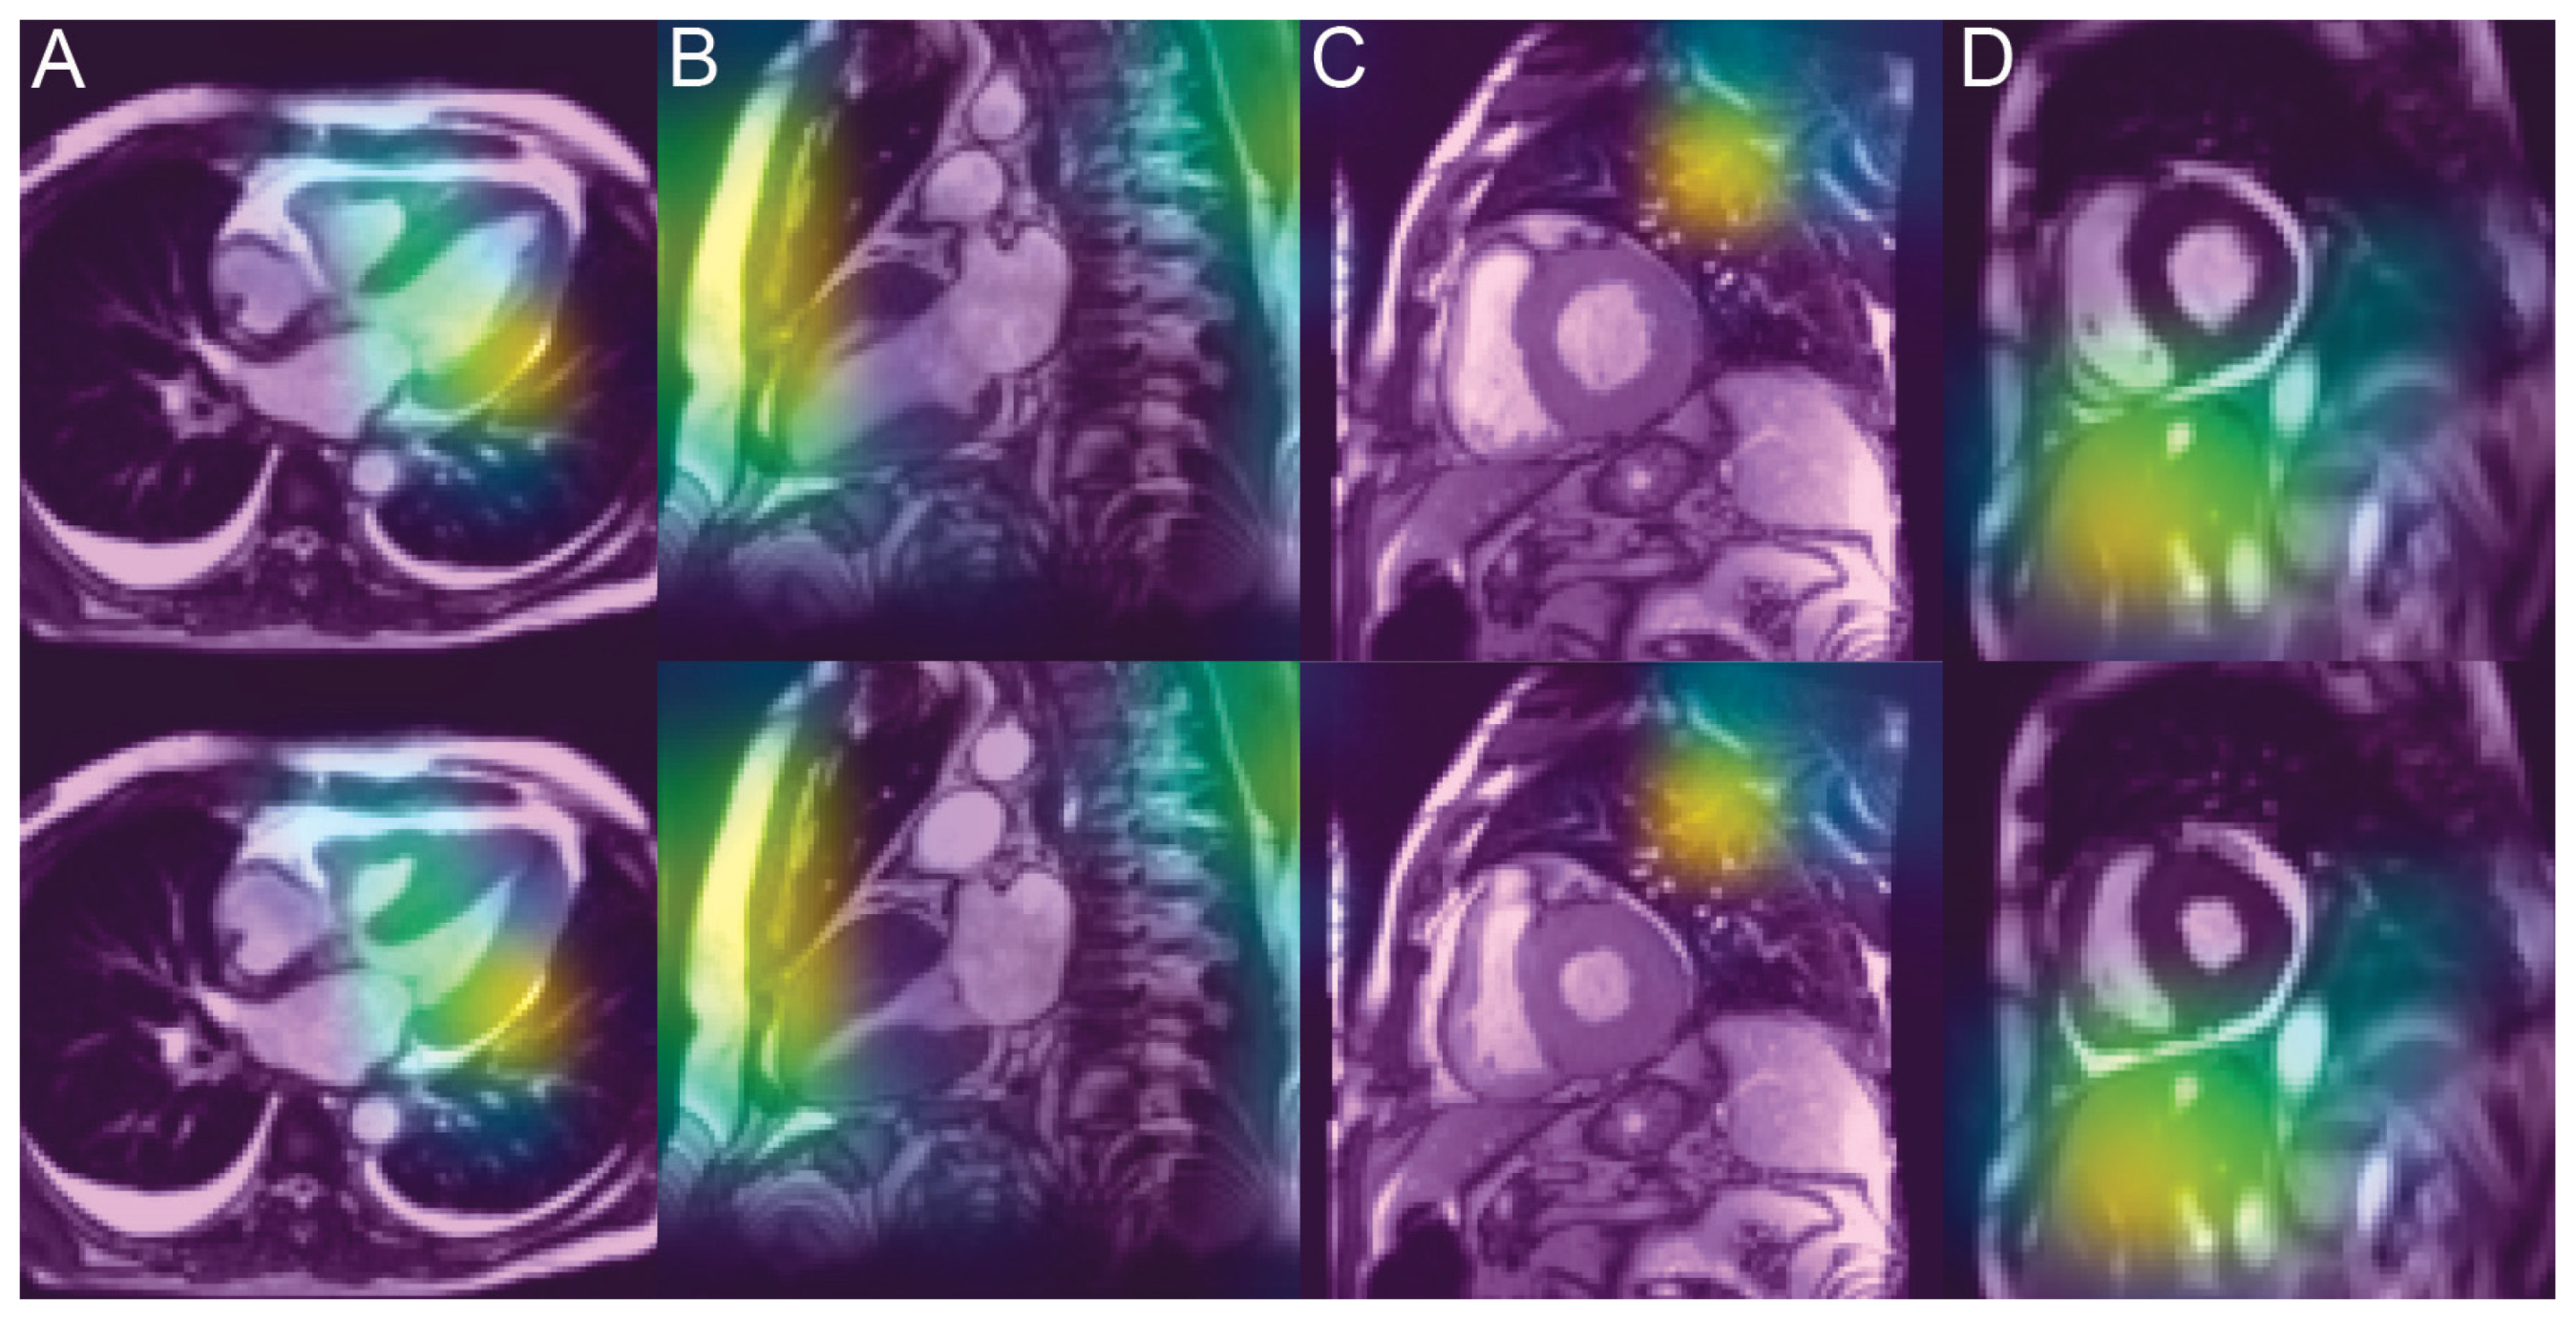

3.4. Analysis of the Saliency Maps